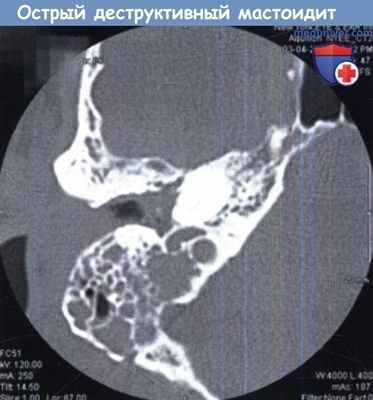

КТ височных костей, на которой определяется деструкция костных перегородок между ячейками сосцевидного отростка.

Острый деструктивный мастоидит.